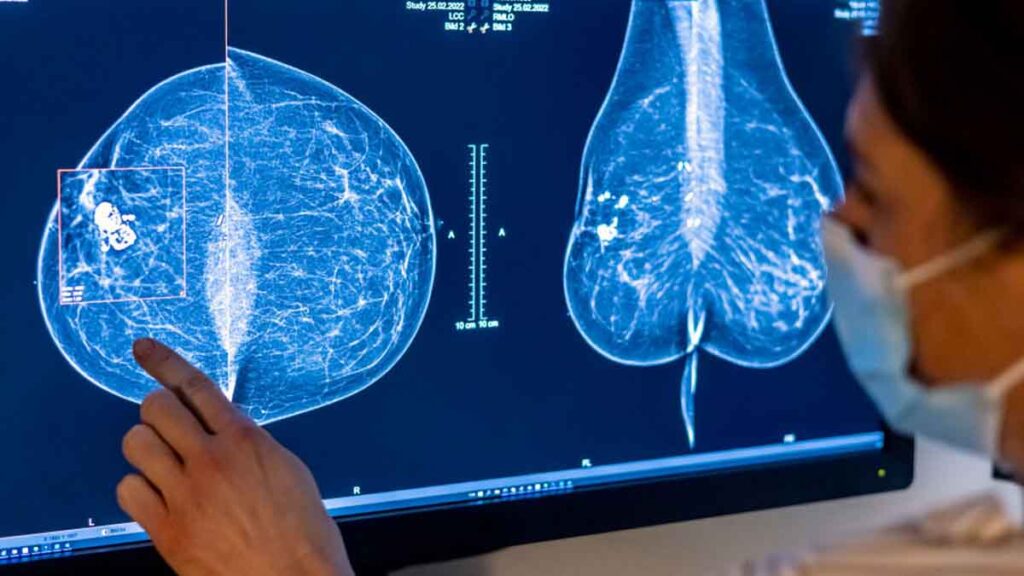

Aproximadamente la mitad de las mujeres mayores de 40 años tienen senos densos, con menos tejido graso y más tejido conectivo y glandular. Ese tejido aparece blanco en las radiografías, del mismo color que los crecimientos en el seno, lo que dificulta la lectura de las mamografías.

Según las nuevas reglas, las mujeres con senos densos recibirán un memorando por escrito que les alertará que su estado “hace que sea más difícil detectar el cáncer de seno”.